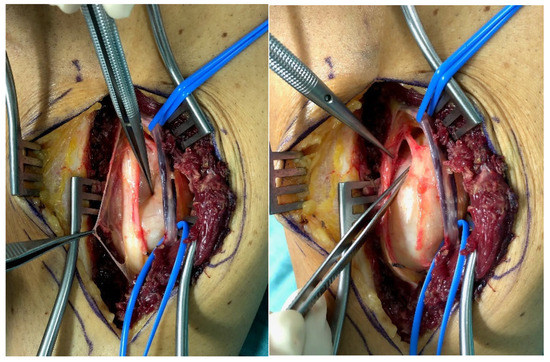

Morphological Relation of Peripheral Nerve Sheath Tumors and Nerve Fascicles: Prospective Study and Classification

Removal of benign peripheral nerve sheath tumors (bPNST) represents a surgical challenge. The morphological relation of bPNST and healthy nerve fascicles are of utmost importance for achieving both removal of the entire tumor and preservation of functional integrity of the peripheral nerve. Thus, [...] Read more.

Removal of benign peripheral nerve sheath tumors (bPNST) represents a surgical challenge. The morphological relation of bPNST and healthy nerve fascicles are of utmost importance for achieving both removal of the entire tumor and preservation of functional integrity of the peripheral nerve. Thus, we intraoperatively assessed the morphological patterns between bPNST and nerve fascicles using photo documentation obtained between January 2009 and September 2021. In 31 patients (20 women and 11 men) with a mean age of 48 ± 18 years a total of 34 bPNST were removed. Four constant morphological patterns between bPNST relatively to nerve fascicles were detected: (1) bPNST is located peripherally (n = 16), (2) it splits the nerve into two main fascicles (n = 5), (3) it totally splits up the nerve out of the nerve’s center (n = 8) und (4) it encloses the nerve and its fascicles (n = 5) without any detectable boundary layer. Histology revealed 28 schwannomas, five neurofibromas, and one perineurioma. The proposed classification reflects the increasing complexity of tumor removal with a higher type number. This might be beneficial for preoperative diagnostics, i.e., high-resolution ultrasound or MRI-tractography, as well as for planning the bPNST’s surgical resection and the possible need for nerve reconstruction. Full article